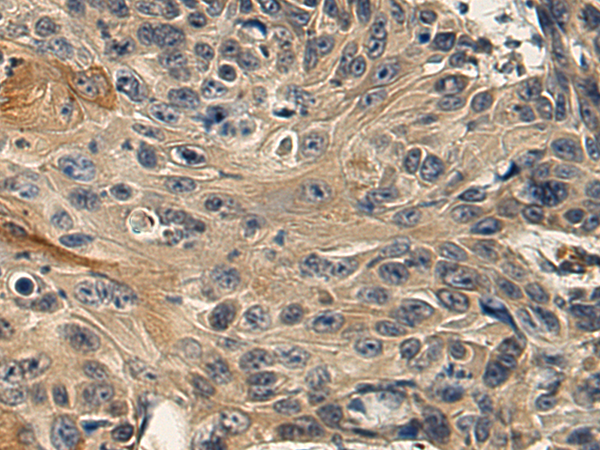

分类: 科研抗体货号: P08945别名: FNRA; CD49e; VLA-5; VLA5A应用: IHC反应种属: Human, Mouse